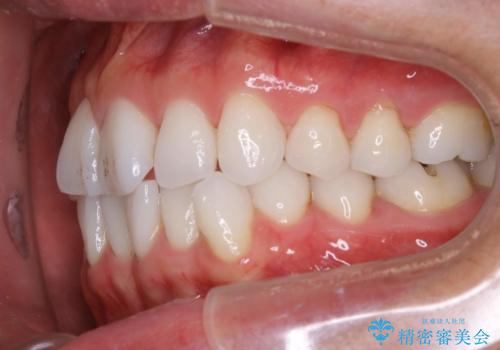

右上の前から2番目の歯が引っ込んで、下の前歯にはガタガタがありました。

上下の歯と歯の間を少量ずつ削りスペースを作り、インビザラインにて並べる計画としました。

目立たずに矯正治療を終えることができたことに満足していただけました。